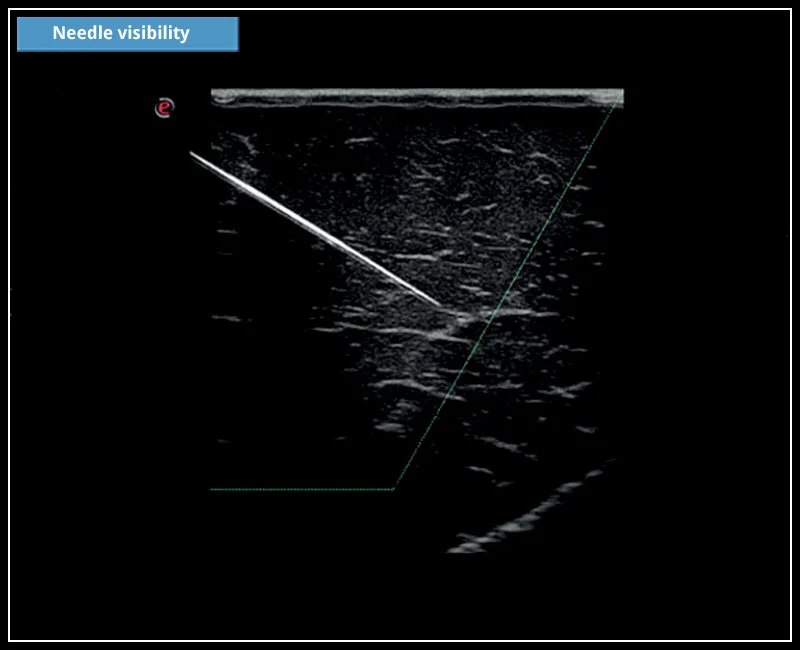

MyLab™X5 - Needle visibility

MyLab™X5 - Needle visibility